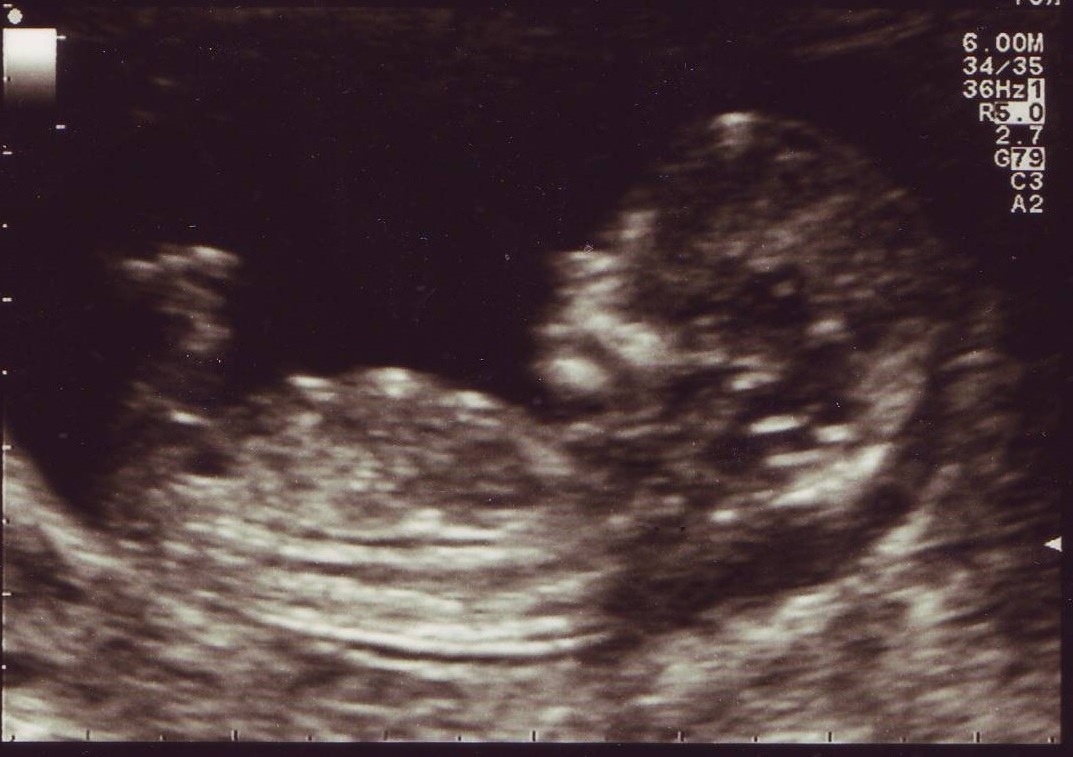

Attachment 7790

Looks girlie.

girl

How many weeks of pregnancy is this?

Thank you so much for your guess.....this was at 12w 3d. Will find out on saturday....soooooooo excited!!!